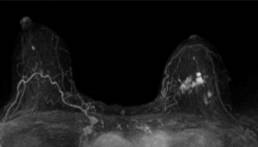

All-in-one case: from screening to pre-operative scans.

Review of the file in a specialized center before surgery showing multicentricity with additional distortion of the internal quadrants ACR5, noted by the Mammoscreen® analysis. The analysis revealed an MRI lesion assembly over 5 cm in height, 2.5 cm in transverse diameter, as well as a non-inflammatory global left breast retraction. The case results in a modification of the surgical pec initially planned with total mastectomy.

Case from the practice of Dr. Daroles